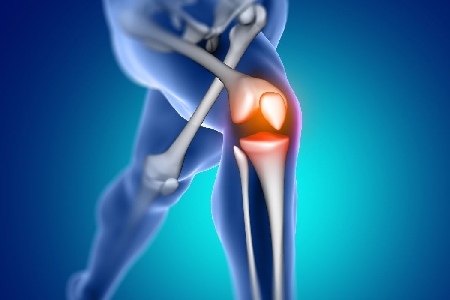

Osteoarthritis can result in joint deformities, particularly in the knees, hips, and hands. Replacement and realignment surgery is performed to relieve pain, restore function, and rehabilitate joint mobility.4) Skeletal Dysplasia